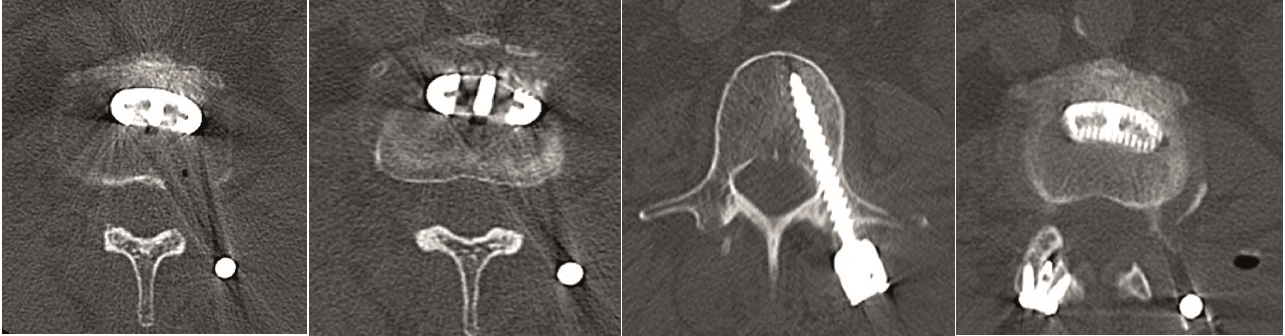

A 40-year-old man 5 years after ALIF L4-L5 using SynFix with axial low back pain. The CT scan shows locked pseudarthrosis (Fig 17). Nonoperative treatment failed. The treatment option was bilateral Facet Wedge at L4-L5.

A less invasive approach was used with Insight Retractor using the bilateral Facet Wedge. No bone graft. X-ray follow-up after 3 months and CT assessment after 6 months (Fig 18-19).